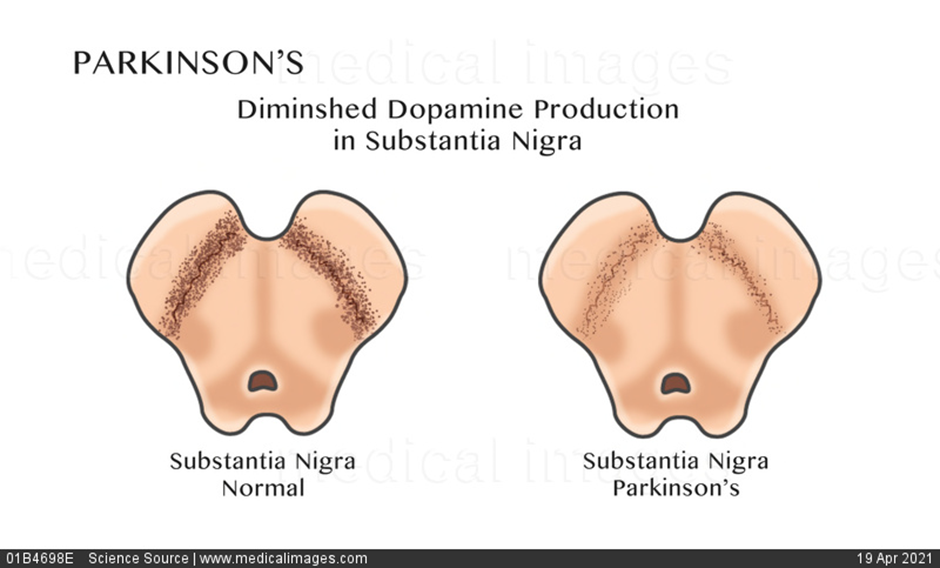

- Parkinson’s disease affects the nerve cells in the substantia nigra of the brain that produce dopamine- a neurotransmitter messenger in the body that allows smooth co-ordinated movements.

- When a person has Parkinson’s disease, these dopamine producing cells start to degenerate and amount of dopamine produced in the brain decreases. Messages from the brain telling the body how and when to move are delivered abnormally, leaving a person incapable of initiating and controlling movements in a normal way.

- It is characterized by loss of approximately 60-80% of the dopamine producing neurons in substantia nigra before the motor symptoms appear, and a profound loss of dopamine in striatum.